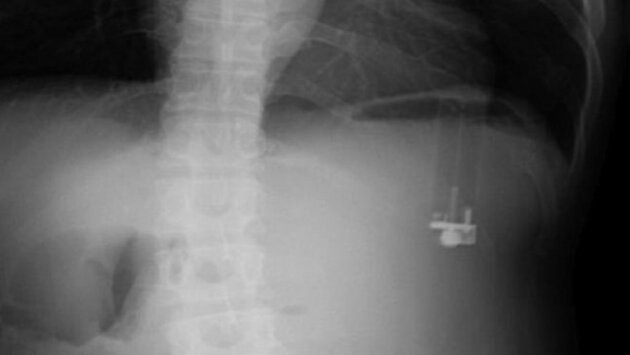

Из желудка 49-летнего шизофреника из Флориды хирурги удалили зажигалку, которая уже начала протекать. Мужчина был доставлен в больницу с жалобами на сильные боли в животе.Потрясенные хирурги одной из больниц Флориды удалили из желудка пациента зажигалку, которая дала протечку и вызвала сильнейшие боли. 49-летний пациент, чье имя не называется по этическим соображениям, страдал от шизофрении и имел привычку глотать инородные предметы, включая ложки. Медики полагают, что случай с зажигалкой является третьим в истории медицины. Она спровоцировала целую серию тяжелейших болей в животе и рвоту, что всё-таки заставило шизофреника обратиться в больницу.Рентгеновские снимки показали наличие инородного предмета, очень напоминающего зажигалку, который находился в желудке. Во время операции по извлечению этого предмета хирурги обнаружили, что из-за утечки зажигалки оболочка органа имеет дырку. Судя по всему, жидкость для зажигалки прожгла слизистую, защищающую стенки желудка от желудочного сока. Впоследствии этот самый сок начал проедать желудочную ткань, что и вызывало резкую боль.Поначалу авторы сообщения об этом случае писали, что обнаруженная ими зажигалка в желудке является первым подобным случаем в медицинской истории. Впоследствии выяснилось, что это уже третий пациент, проглотивший зажигалку. Через два месяца после операции он явился на профилактический осмотр, во время которого было установлено, что желудок полностью зажил. Изучение медицинской истории пациента показало, что ранее он проглатывал ложки, а также бритвенные лезвия. Всякий раз это требовало госпитализации и длительного лечения.